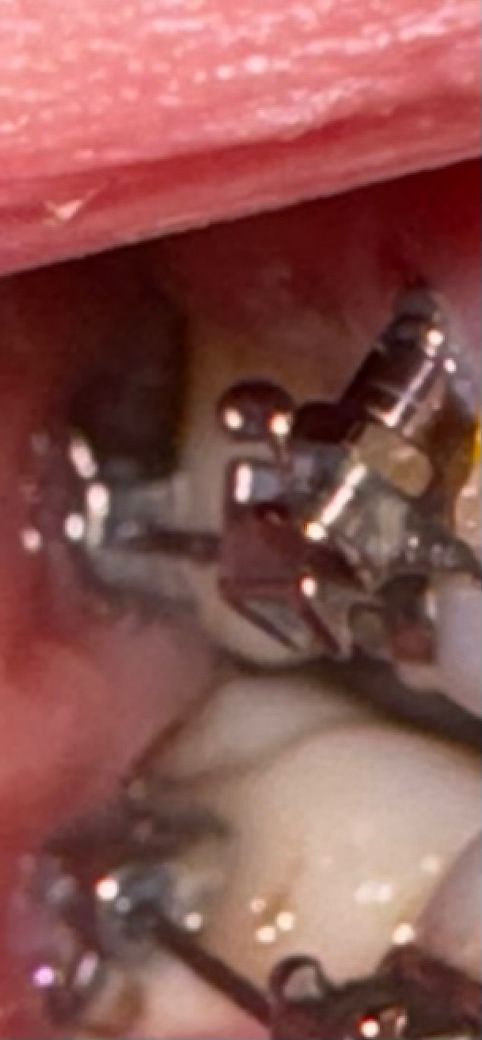

교정중인데 잇몸 나사가 떨어지려고합니다

저번달에 검사 받았을때도 흔들리고 있다고 해서 이번달 검사까지 한번 보고 다시 박던가 두던가 하자고 했었는데 오늘 보니까 잇몸에 쓸리니까 점점 빠지는것 같더라고요ㅠㅠ

방금 보니까 거의 밖으로 나왔던데 목요일에 병원에 가려는데 만약 빠질것 같으면 자연스럽게 빠지게 냅두는게 좋겠죠?

• 1번 째 사진

자연스럽게 빠지기 전에 빼는 것이 좋습니다. mini-screw가 빠질 정도라면 해당 부위에 염증이 있다는 것이며 염증으로 인한 불편감이 심해질 수 있습니다. 심한 경우에는 농의 형태로 나올 수도 있으므로 최대한 치과를 빨리 방문하여 제거하는 것이 좋습니다.

교정 스크류 많이 빠져나온 상태로 보이며 삼킬 수도 있기에 조심하셔야합니다. 빠른시일 내에 병원내원하시기를 바랍니다.